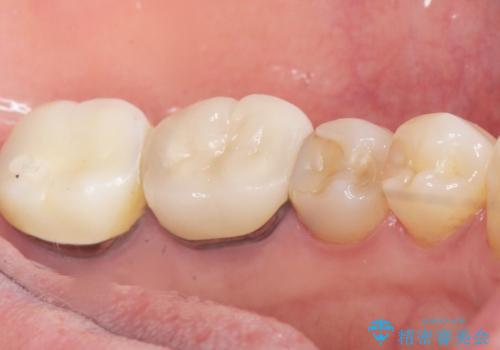

古い詰め物とう蝕を除去し、審美的で適合が良く二次う蝕になりにくいセラミックインレーによる修復を行いました。

審美的な仕上がりと自然な咬み心地に喜んで下さいました。

インレーの種類:セラミックインレー(e-max press)